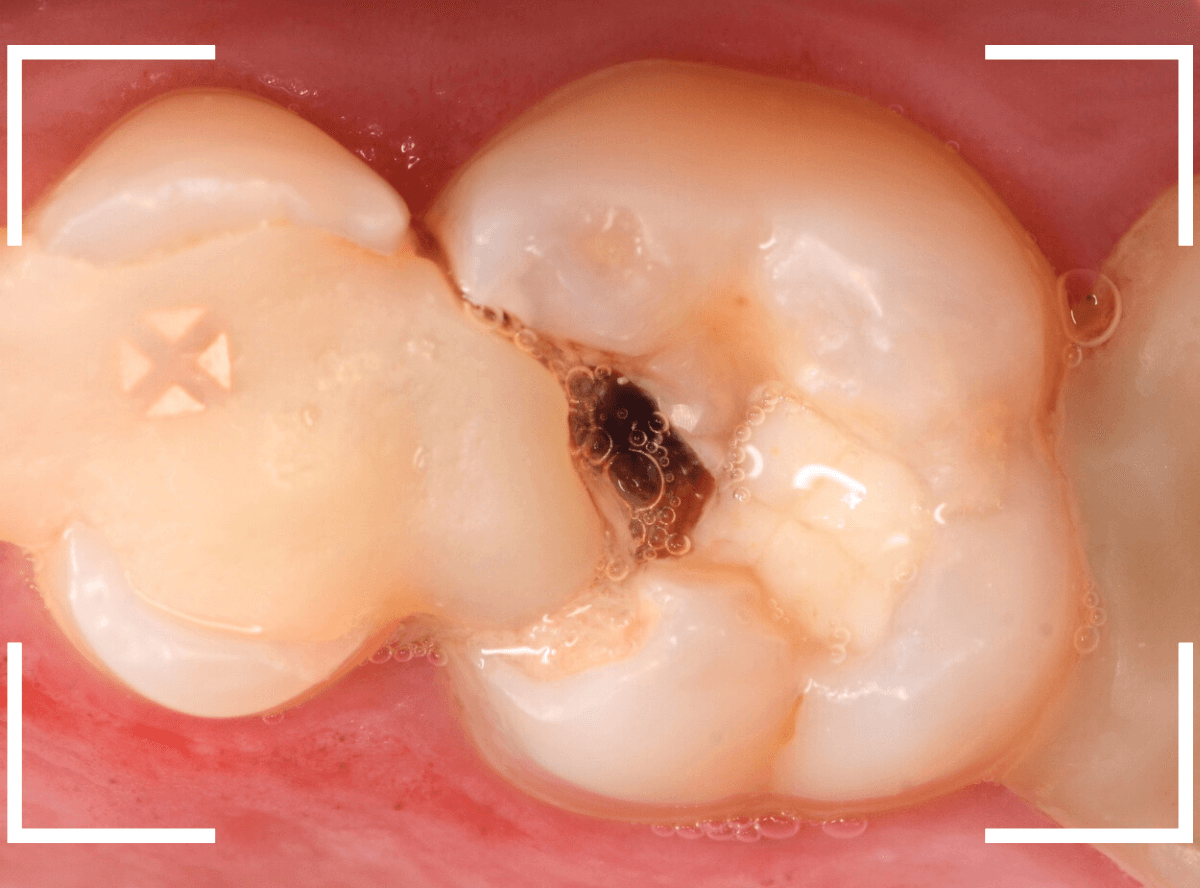

Case.10 隣の歯とのすき間につめた、レジンの中の虫歯

こちらも、他の歯の治療希望で来院された患者さんです。

歯と歯の間につまっているレジンがかけています。

中が黒くぼやっとしているので、おそらく虫歯になっていると思われます。

レントゲン写真で確認します。

レジンを外すと、中の虫歯が出てきました。

虫歯を全て除去しました。

思ったよりも中で虫歯が広がっていました。

隣りの歯にも、虫歯は写っていました。

・自覚症状なし

・つめものの下が虫歯

・隣の歯との虫歯

・治療したら、隣の歯も虫歯

と、典型的な虫歯の例でした。